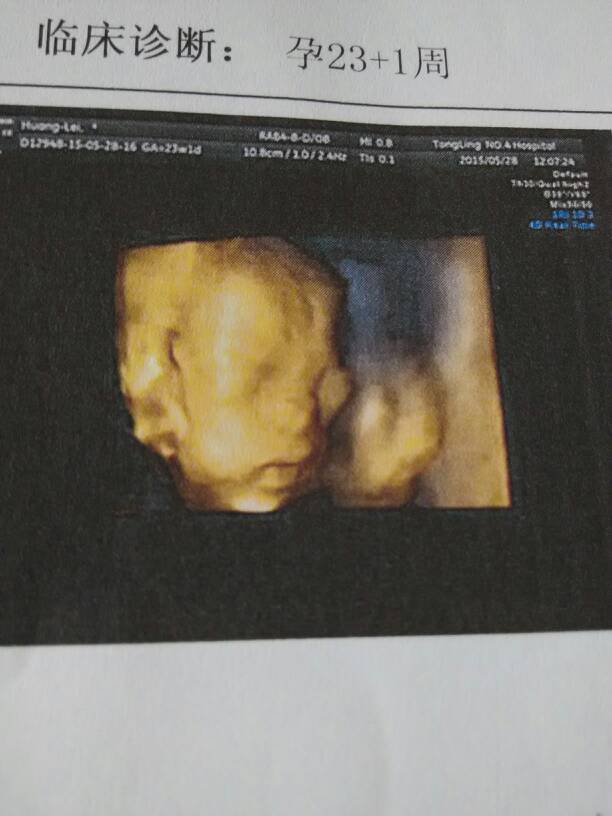

四维彩超回来,超声提示胎儿左右心室各一枚强光点,建议复查 请问要不要紧?

四维彩超回来,超声提示胎儿左右心室各一枚强光点,建议复查。请问要不要紧?

你好:心室强光点一般无实际意义的,宝妈不用担心什么,建议全面营养,注意休息。